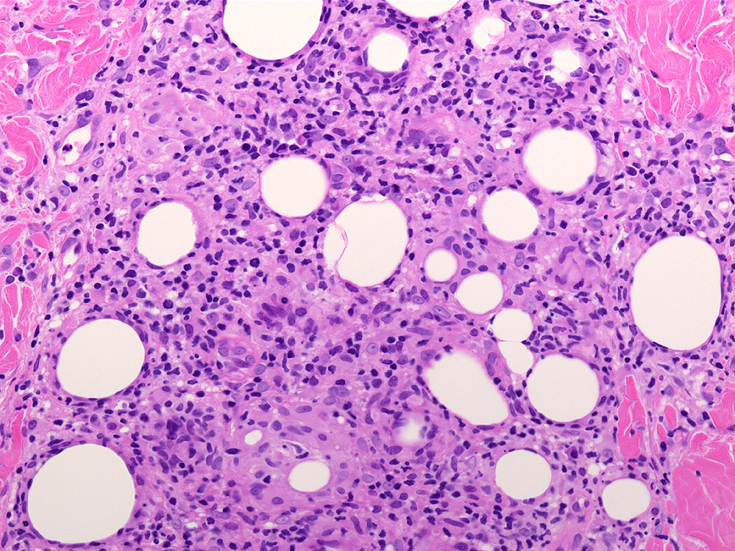

リンパ腫の定義: SPTCLは成熟細胞障害性T細胞(cytotoxic T-cell)由来で、皮下組織に脂肪識炎に似た組織像を呈しながら増殖する悪性リンパ腫。

組織所見*16*17*18

皮下組織に優位な, 小~中型 Tリンパ球の密な浸潤が特徴。ときに大型リンパ球や組織球が混在する。 リンパ球の異型は, わずかなものから明瞭な異型を示す症例までさまざまである。